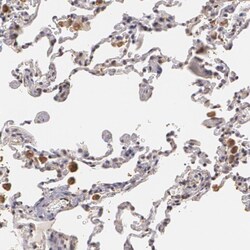

PA5-81949 IHC

Full details

Method: